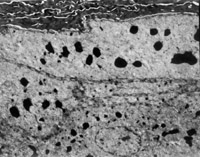

經(jīng)MEBT/MEBO治療20天,電鏡觀察到基底細胞層與纖維母細胞之間的半橋粒連接,同時可見纖維母細胞內(nèi)粗面內(nèi)質網(wǎng)結構和線粒體增生活躍(圖5-3-19~5-3-21)。 MEBT/MEBO治療30天后,上皮組織再生修復,已基本完成,創(chuàng)面組織切片顯示膠原纖維成熟,排列整齊(圖5-3-22),直徑為0.1~0.5祄,并可見明暗相間周期性橫紋(64nm),未見到膠原纖維扭曲和呈旋渦、菜花等病理形態(tài)。

5-3-22 MEBT/MEBO治療30天,整齊排列的膠原纖維,纖維均勻一致直 徑 0.1~0.5祄,有明暗相間的周期性橫紋(64nm)